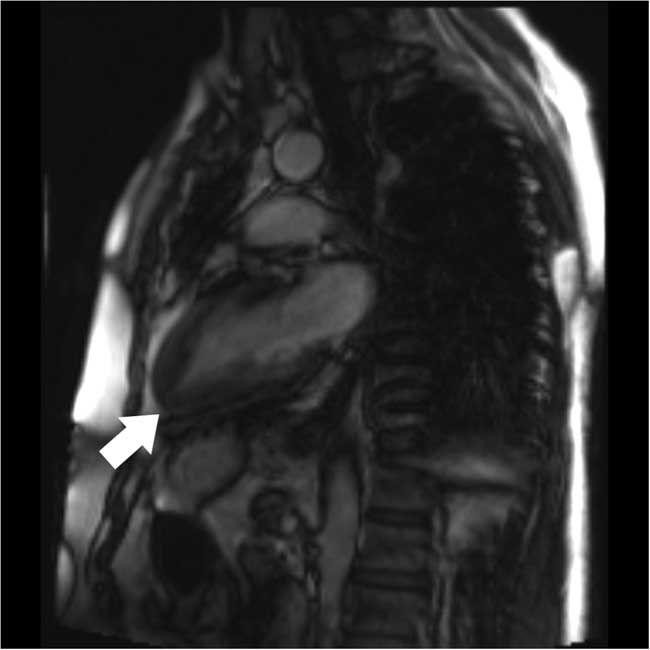

Four months later, the patient was seen at an outpatient follow-up by his cardiologist and was well. Oral metoprolol was continued. Cardiac magnetic resonance imaging (MRI) was suboptimal but appeared to show an “ace-of-spades” configuration (Figure 4). A repeat transthoracic echocardiogram confirmed ApHCM with a progressive increase in wall thickness toward the apex with a wall thickness greater than 15 mm. A 24-hour Holter monitor showed predominantly a sinus rhythm with infrequent asymptomatic premature atrial contractions and no ventricular ectopy.

Figure 4 Cardiac magnetic resonance imaging demonstrating progressive thickening of myocardium toward the left ventricular apex (white arrow)